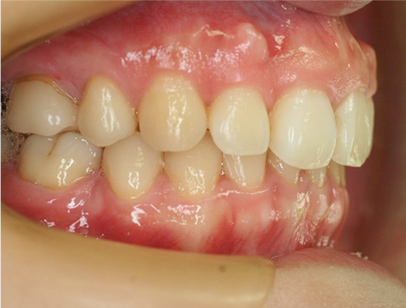

• 左側

• 右側